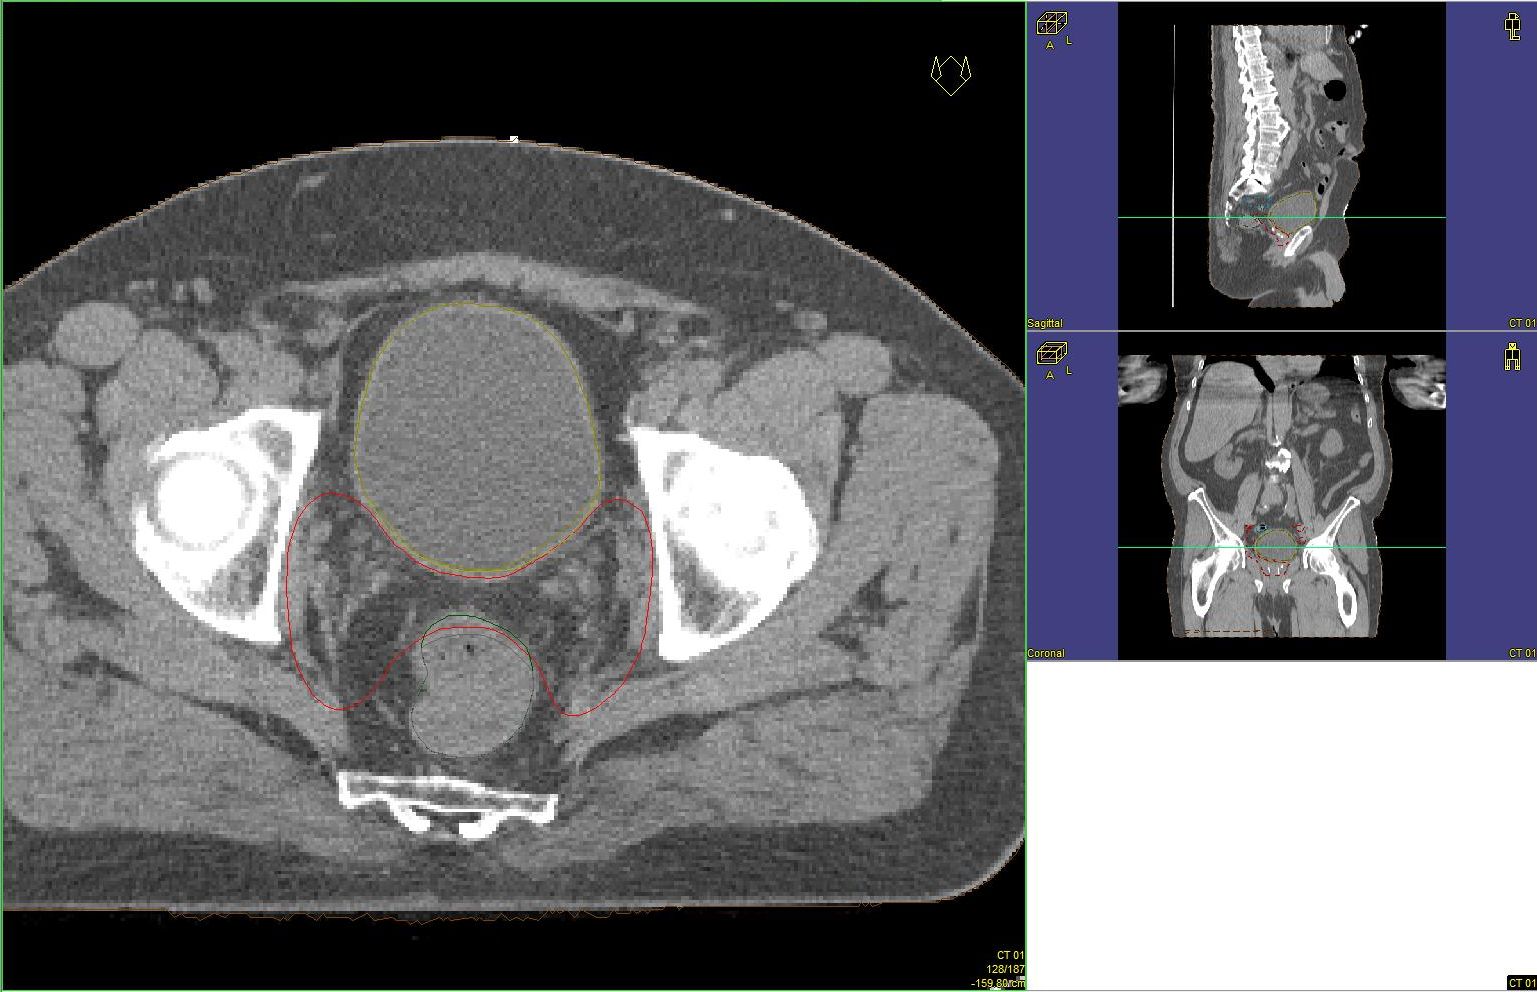

Prostata-Ca: Zielvolumen der postoperativen Radiotherapie

Beispiel: postoperative RT